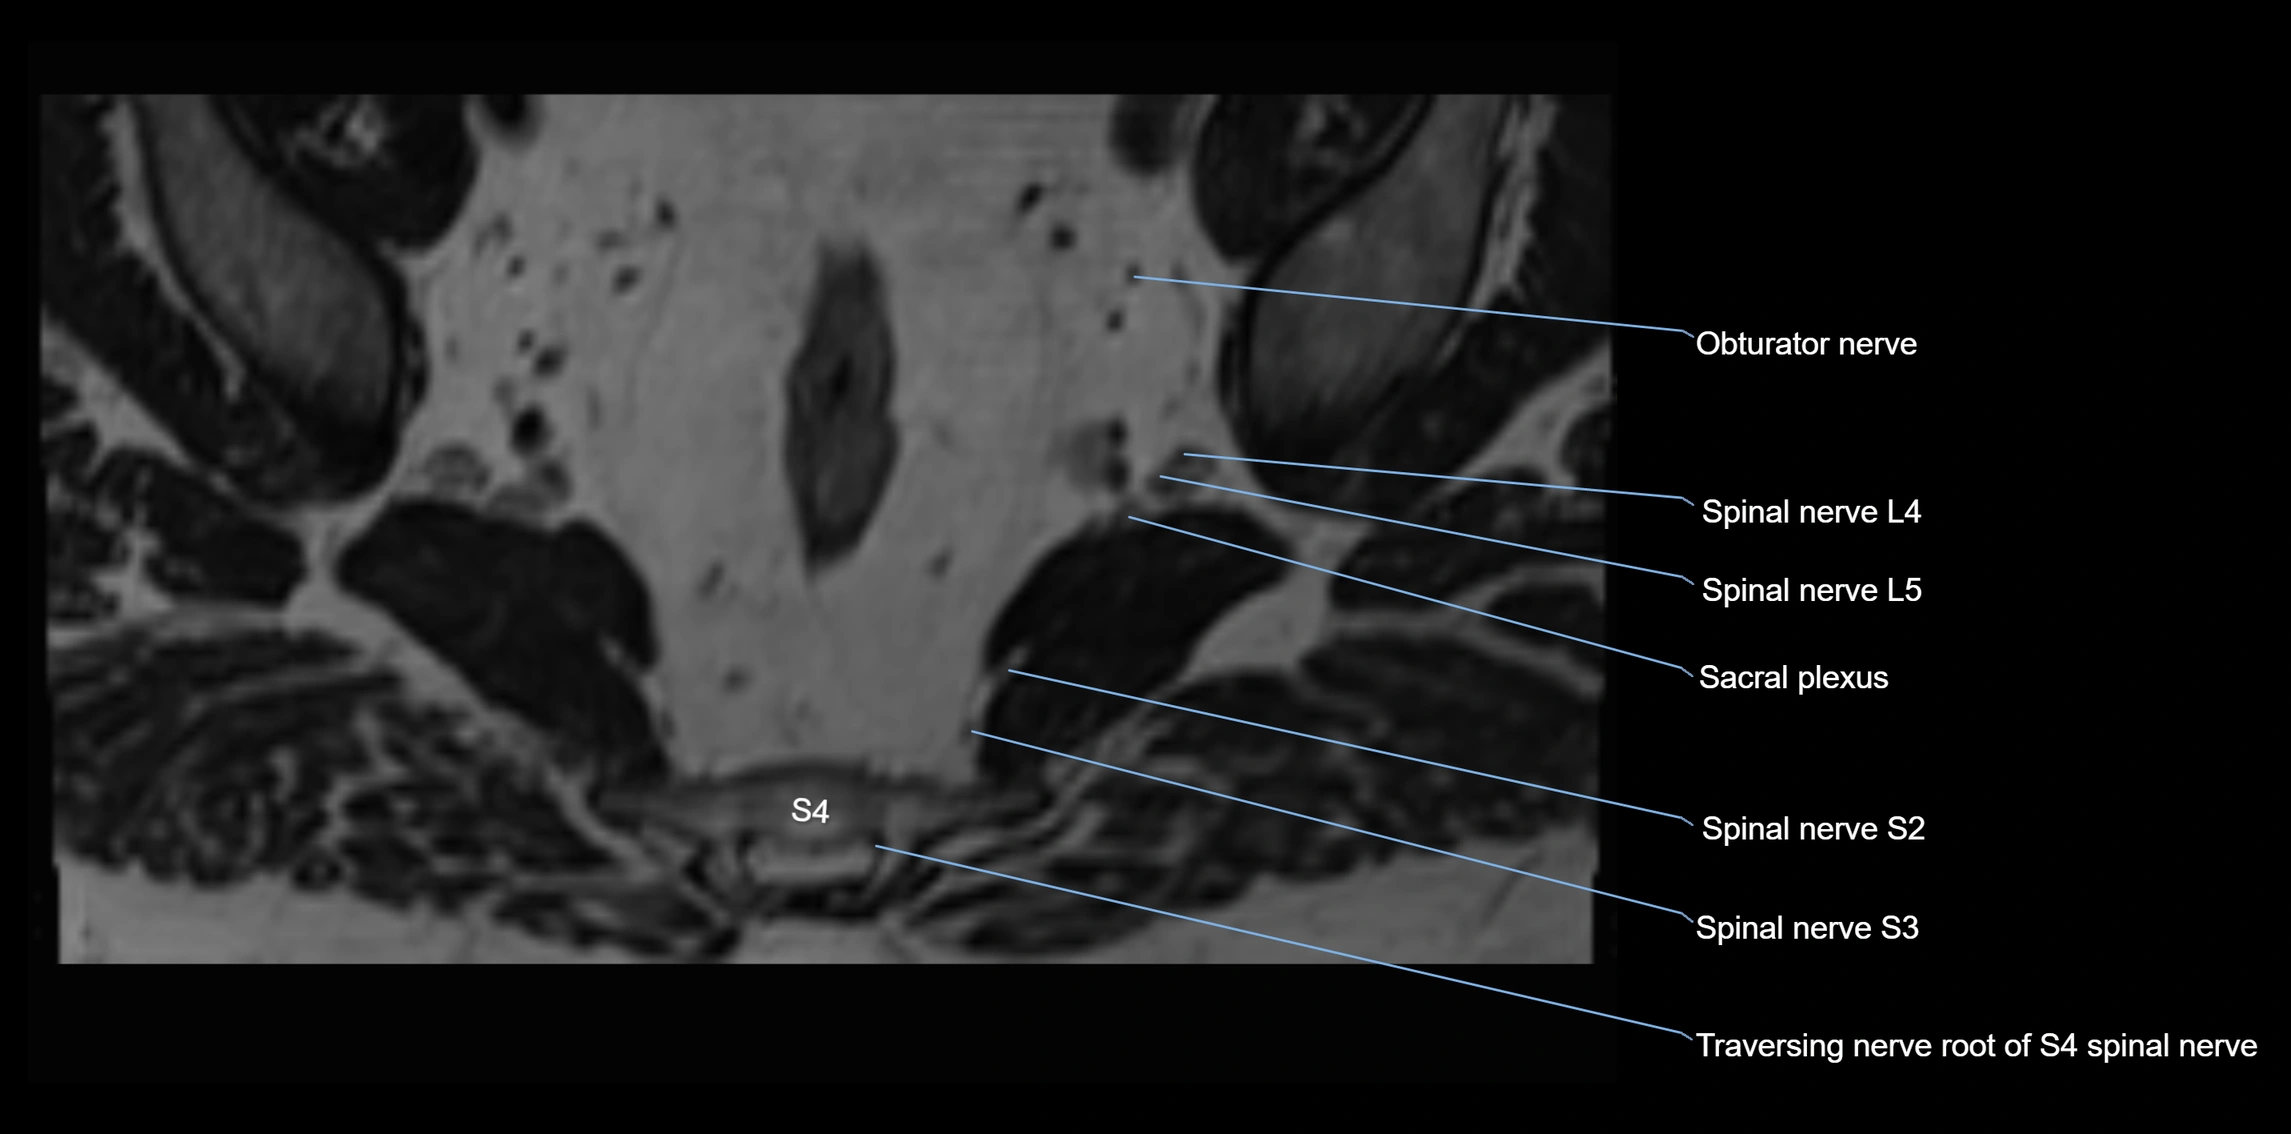

MRI Appearance

T1-weighted images:

• Nerve appears as a very thin low-to-intermediate signal intensity structure

• Surrounded by bright fat, aiding visualization

T2-weighted images:

• Nerve shows intermediate to mildly hyperintense signal compared to muscle

• Pathological involvement appears brighter

STIR (Short Tau Inversion Recovery):

• Normal nerve appears dark

• Inflamed or entrapped nerve appears bright hyperintense

T1 Fat-Sat Post-Contrast:

• Normal nerve enhances minimally

• Pathologic nerve (neuritis, entrapment, tumor infiltration) shows focal or diffuse enhancement

3D T2 SPACE / CISS:

• Nerve appears intermediate to mildly hyperintense compared to muscle

• Surrounded by bright fat or CSF, improving visualization

• Best sequence for mapping small pelvic nerves such as the anococcygeal